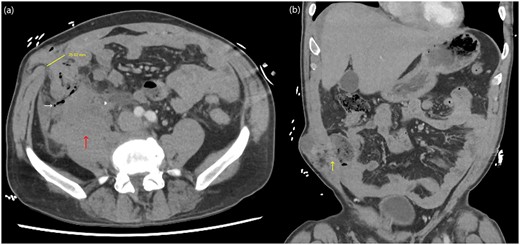

A computed tomography (CT) trauma series scan of his abdomen (Fig. 1) revealed an acute traumatic spigelian hernia through a 25 mm defect containing his caecum as well as caecal bruising and free fluid in the right paracolic gutter. He was also found to have an estimated 500 mL retroperitoneal haematoma anterior to the right psoas with overlying gas (Fig. 2). Given the suspicion for bowel perforation secondary to the acute traumatic spigelian hernia, emergency surgery was immediately organized.

Abdominal CT axial (a) and coronal slices (b) demonstrating a 25 mm defect in the anterior abdominal wall lateral to rectus abdominis in the right lower quadrant containing caecum with adjacent small locules of extraluminal gas as well as a right-sided retroperitoneal haematoma.